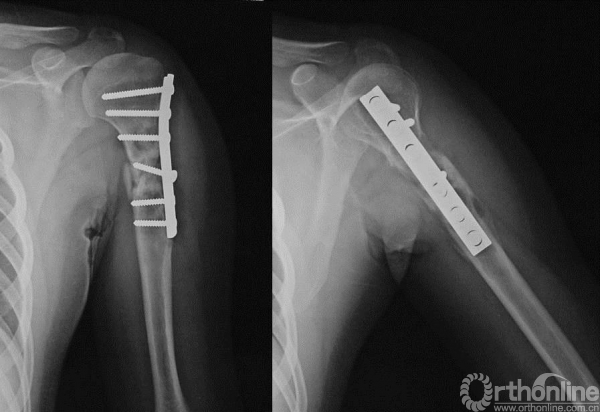

图13-8 病例一入院时X线平片正侧位(第一次术后6个月)

图13-11 病例一第二次术后X线平片正位

图13-14 病例一第二次术后4个月X线平片正侧位(第一次术后10个月)

图13-15 病例二术后17个月X线平片正侧位